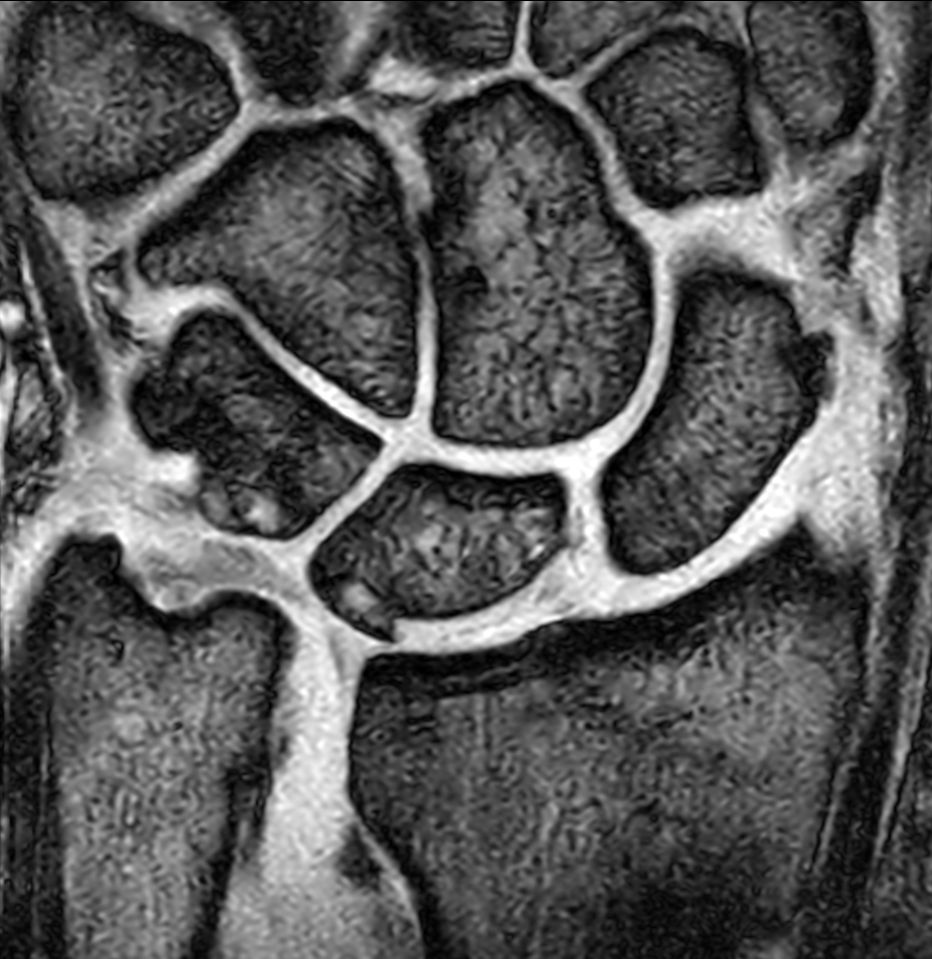

Patient with a lesion in his wrist. dS Microscopy coil set is used, consisting of two 47 mm coils, for small field-of-view imaging with high in-slice spatial resolution and a high signal-to-noise ratio. Compressed SENSE is used in all sequences to shorten the overall exam time for the patient.

Coronal 3D T1w TSECompressed SENSE